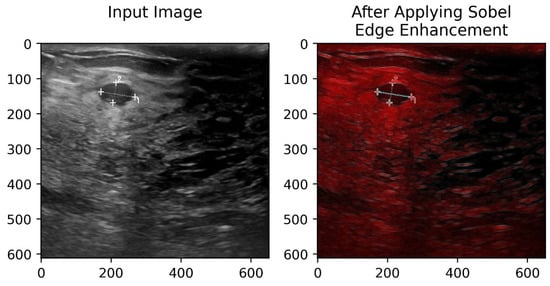

3.3.1. Sobel Edge Augmentation

In order to extract important gradient details from the input images, the model starts with a Sobel-based edge enhancement [39] layer. The Sobel operator is applied to emphasize lesion boundaries by detecting prominent intensity changes that are often difficult to distinguish in breast ultrasound and skin lesion images. By incorporating these edge maps as additional input channels, the network is encouraged to focus on boundary-related features, leading to more accurate segmentation, particularly in areas with low contrast and complex or irregular lesion shapes. This step helps the network focus more effectively on key structural details, such as edges and contours, which is particularly important for distinguishing between different types of distractions.

To better locate edge information from the feature maps, we designed an attention module that enhances edge response. Initially, the module applies horizontal and vertical Sobel operators to the feature map individually to obtain edge gradient maps. Then, it computes edge intensities from these two gradient maps to generate a new feature map representing the edge strength at each pixel. Subsequently, the feature map with edge intensities undergoes a pooling operation. Finally, the weight vector obtained after passing through fully connected layers is applied to the original image via element-wise multiplication. This application of calculated weights across each channel of the feature map amplifies the response of important channels while suppressing that of less important ones, as detailed in Figure 4. The application of Sobel edge enhancement is further illustrated in Figure 5.

Figure 5. Input image and its edge representation obtained using the Sobel operator.